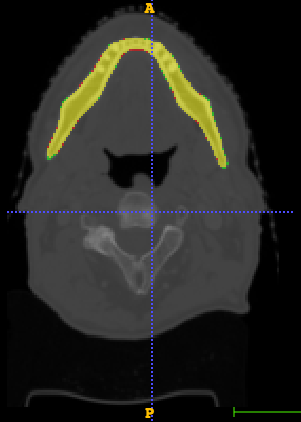

In Chapter 6, we propose an end-to-end, atlas-free 3D convolutional deep learning framework for fast and fully automated whole-volume HaN anatomy segmentation [115]. Our deep learning model, called AnatomyNet, segments OARs from head and neck CT images in an end-to-end fashion, receiving whole-volume HaN CT images as input and generating masks of all OARs of interest in one shot. AnatomyNet is built upon the popular 3D U-net architecture, but extends it in three important ways: 1) a new encoding scheme to allow auto-segmentation on whole-volume CT images instead of local patches or subsets of slices, 2) incorporating 3D squeeze-and-excitation residual blocks in encoding layers for better feature representation, and 3) a new loss function combining Dice scores and focal loss to facilitate the training of the neural model. These features are designed to address two main challenges in deep-learning-based HaN segmentation: a) segmenting small anatomies (i.e., optic chiasm and optic nerves) occupying only a few slices, and b) training with inconsistent data annotations with missing ground truth for some anatomical structures. We collect 261 HaN CT images to train AnatomyNet, and use MICCAI Head and Neck Auto Segmentation Challenge 2015 as a benchmark dataset to evaluate the performance of AnatomyNet. The objective is to segment nine anatomies: brain stem, chiasm, mandible, optic nerve left, optic nerve right, parotid gland left, parotid gland right, submandibular gland left, and submandibular gland right. Compared to previous state-of-the-art results from the MICCAI 2015 competition, AnatomyNet increases Dice similarity coefficient by 3.3% on average. AnatomyNet takes about 0.12 seconds to fully segment a head and neck CT image of dimension , significantly faster than previous methods. In addition, the model is able to process whole-volume CT images and delineate all OARs in one pass, requiring little pre- or post-processing. We demonstrate that our proposed model can improve segmentation accuracy and simplify the auto-segmentation pipeline. These contributions are released as an open-source software package called AnatomyNet, which is publicly available555https://github.com/wentaozhu/AnatomyNet-for-anatomical-segmentation. Portions of this chapter were published as part of [115].